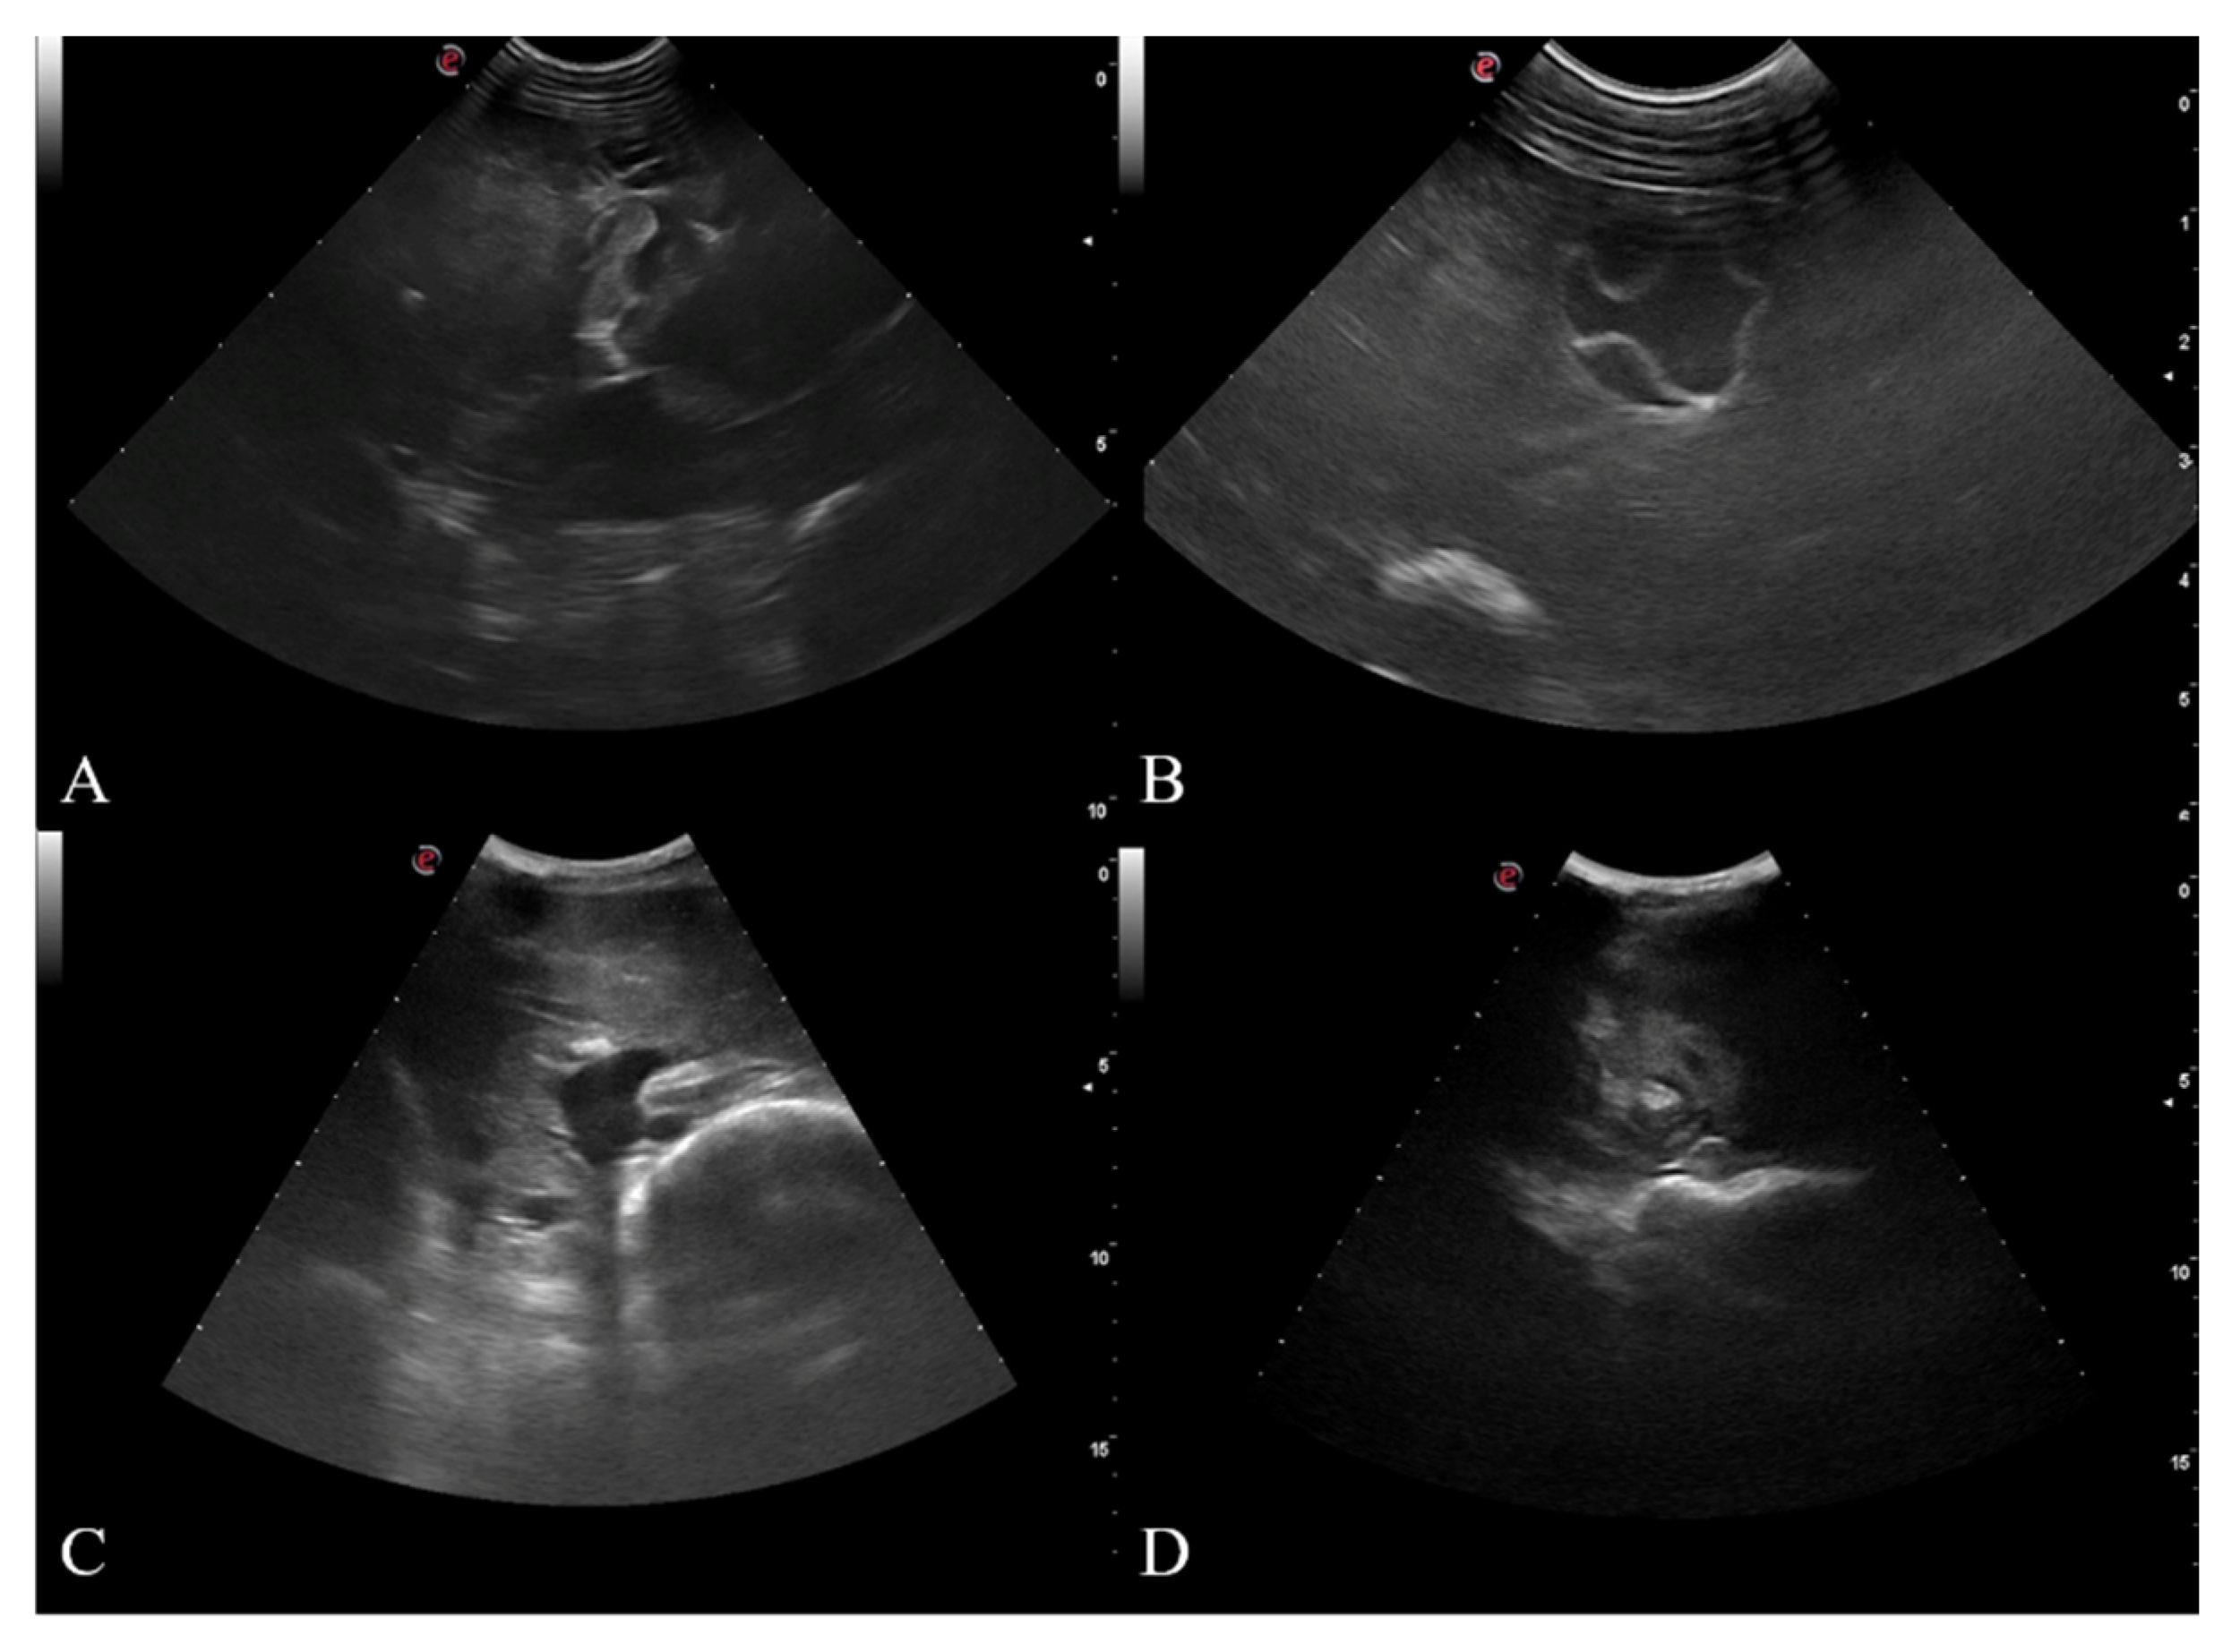

- CL: unilocular anechoic cystic lesion with uniform anechoic content. The cyst wall is not visible.

- CE1: uniformly anechoic cyst with uniform anechoic content or fine internal echoes.

- CE2: cyst with internal septation, sometimes with a honeycomb appearance

- CE3: unilocular cyst that can show the presence of a daughter cyst.

- CE4: hypoechoic and hyperechoic matrix, the appearance resembles a ball of wool.

- CE5: cyst with partially or completely calcified wall.